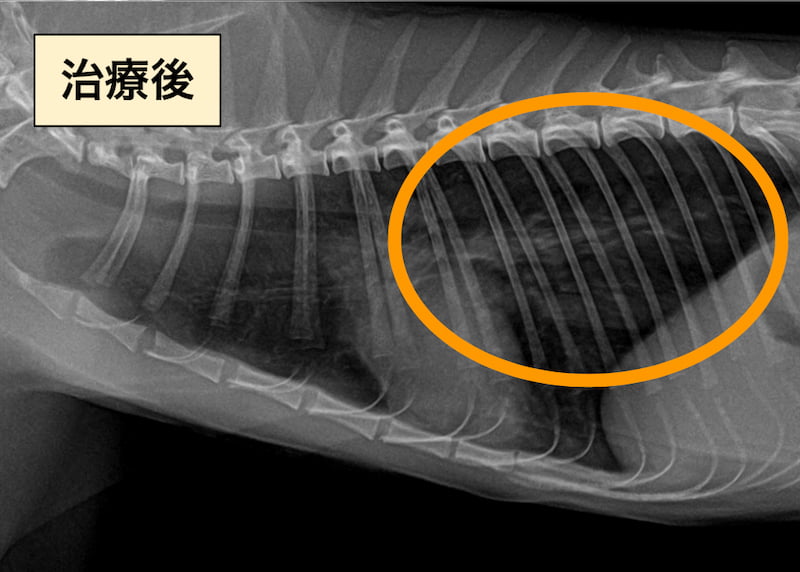

下の画像が治療後のレントゲン検査の画像です。

治療後は気管支パターンが改善していました。

この症例ではすぐに呼吸が落ち着き、その後は症状の波はあありますが、支持療法としてエアロキャット(猫用のスペーサー)による吸入ステロイドを中心に治療を継続しています。